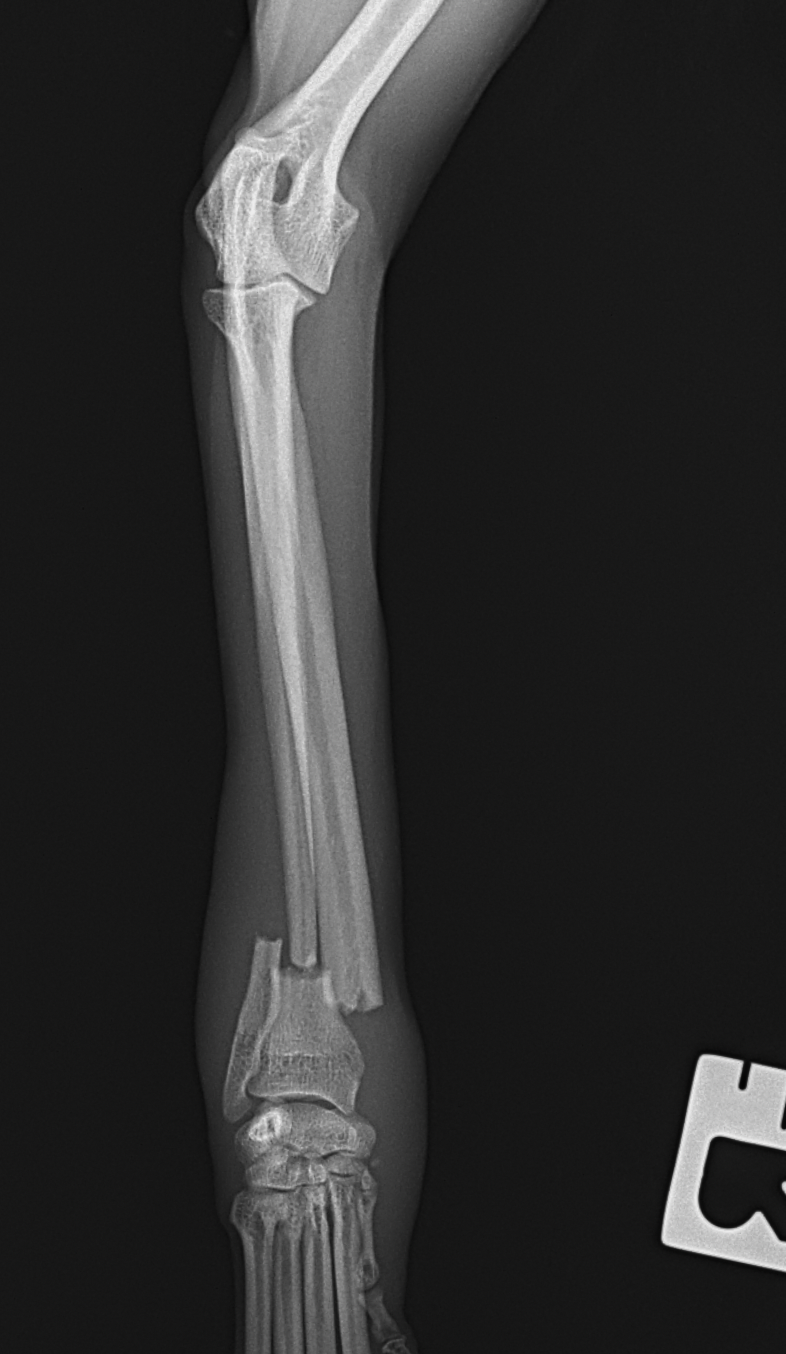

橈骨固定術 #248

小型犬が室内でジャンプして着地に失敗し、前肢を痛がり始めたとの事。かかりつけ医で橈尺骨遠位端骨折が確定されました。整復を目的に当院を受診されました。1.5 Titanium Locking Plateを用いて固定術を行いました。しばらく安静が必要です。